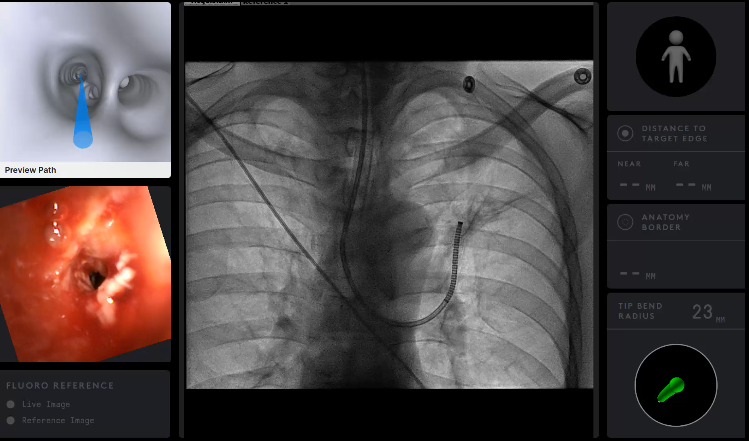

Ramsy Abdelghani, MD@Rabdelgh·

Cool case: 4.5mm partially solid PET-Avid LLL nodule. Used High PEEP/Tidal volume and wedged left side up to decrease dependent atelectasis. Navigated with Ion and adjusted with Philips CBCT. ROSE positive for Adenocarcinoma. Exciting times in lung cancer care! #ION #cbct